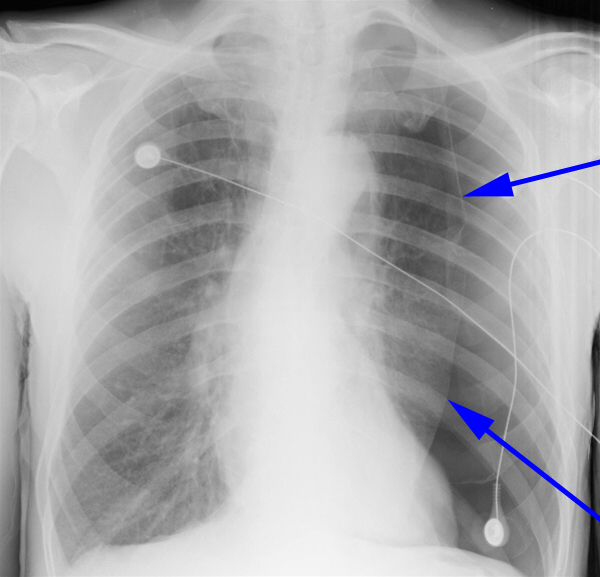

Lunger, røntgen, spontan pneumothorax

Røntgenbilledet viser en venstresidig pneumothorax, hvor lungens volumen er reduceret til ca. det halve. Lungehinden (Pleura viscerale) er klart synlig, og hjertet er forskudt mod højre side.